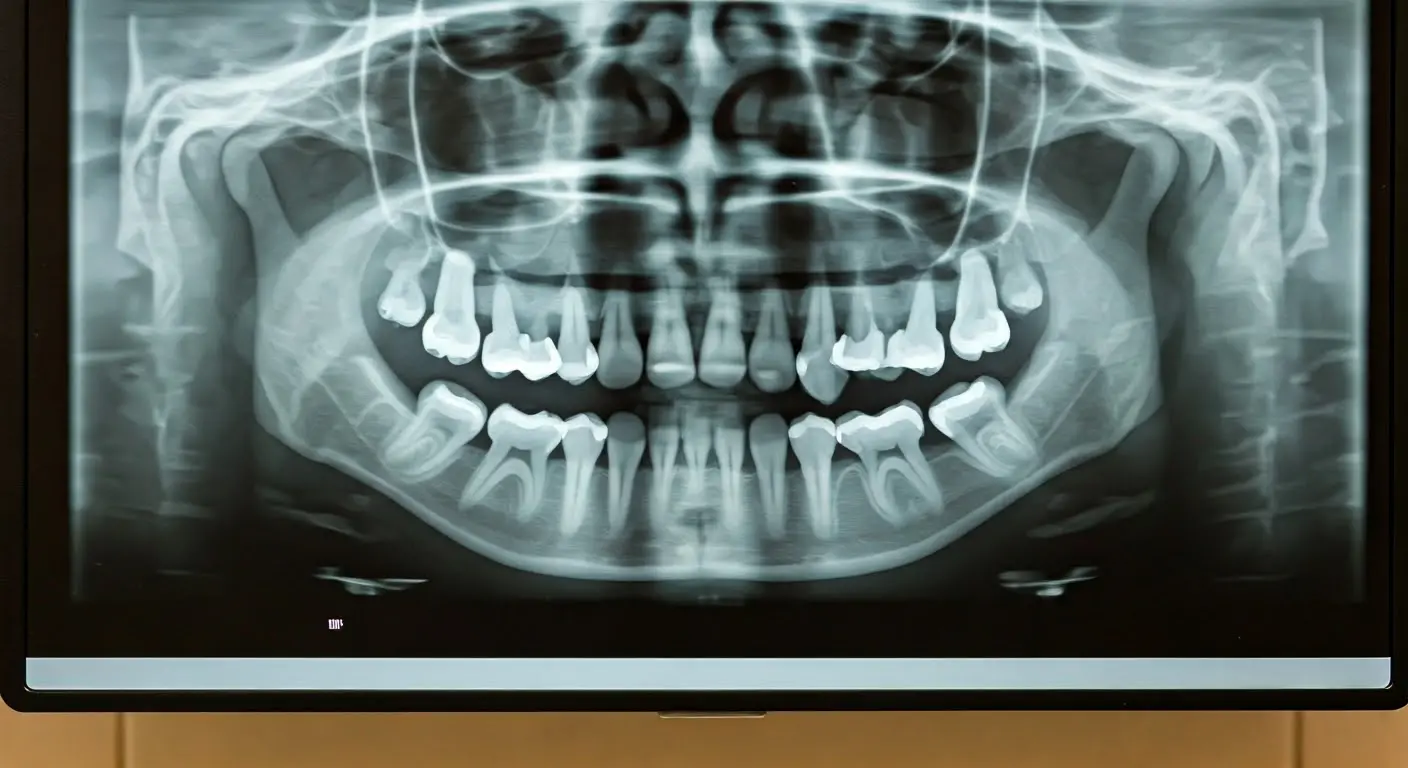

Dental X-rays

Essential for accurate diagnosis.